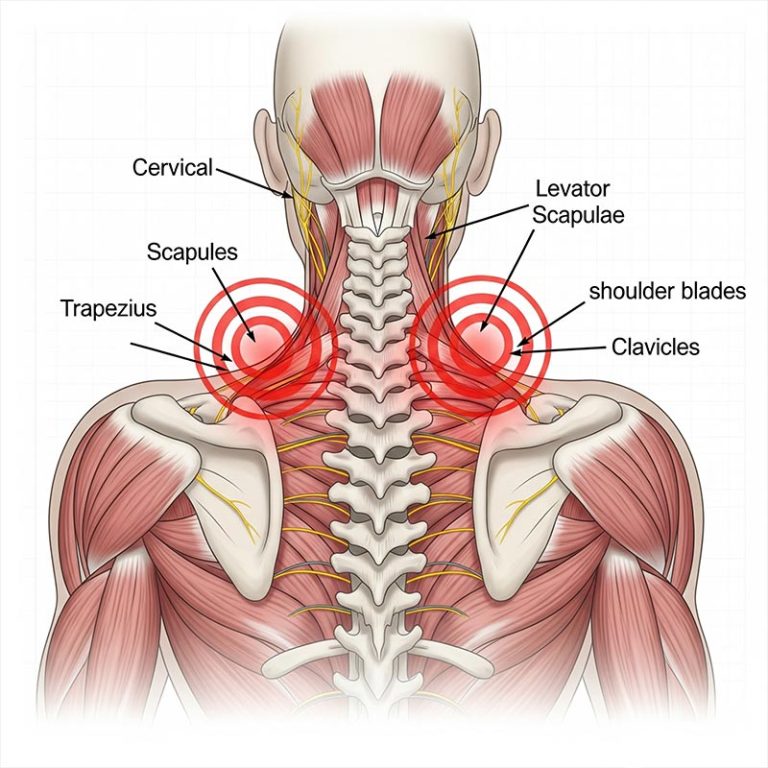

Upper back pain is a common issue that affects the area between the neck and the lower back, often caused...

Headaches with neck pain are often linked to muscle tension, poor posture, or stress, commonly known...